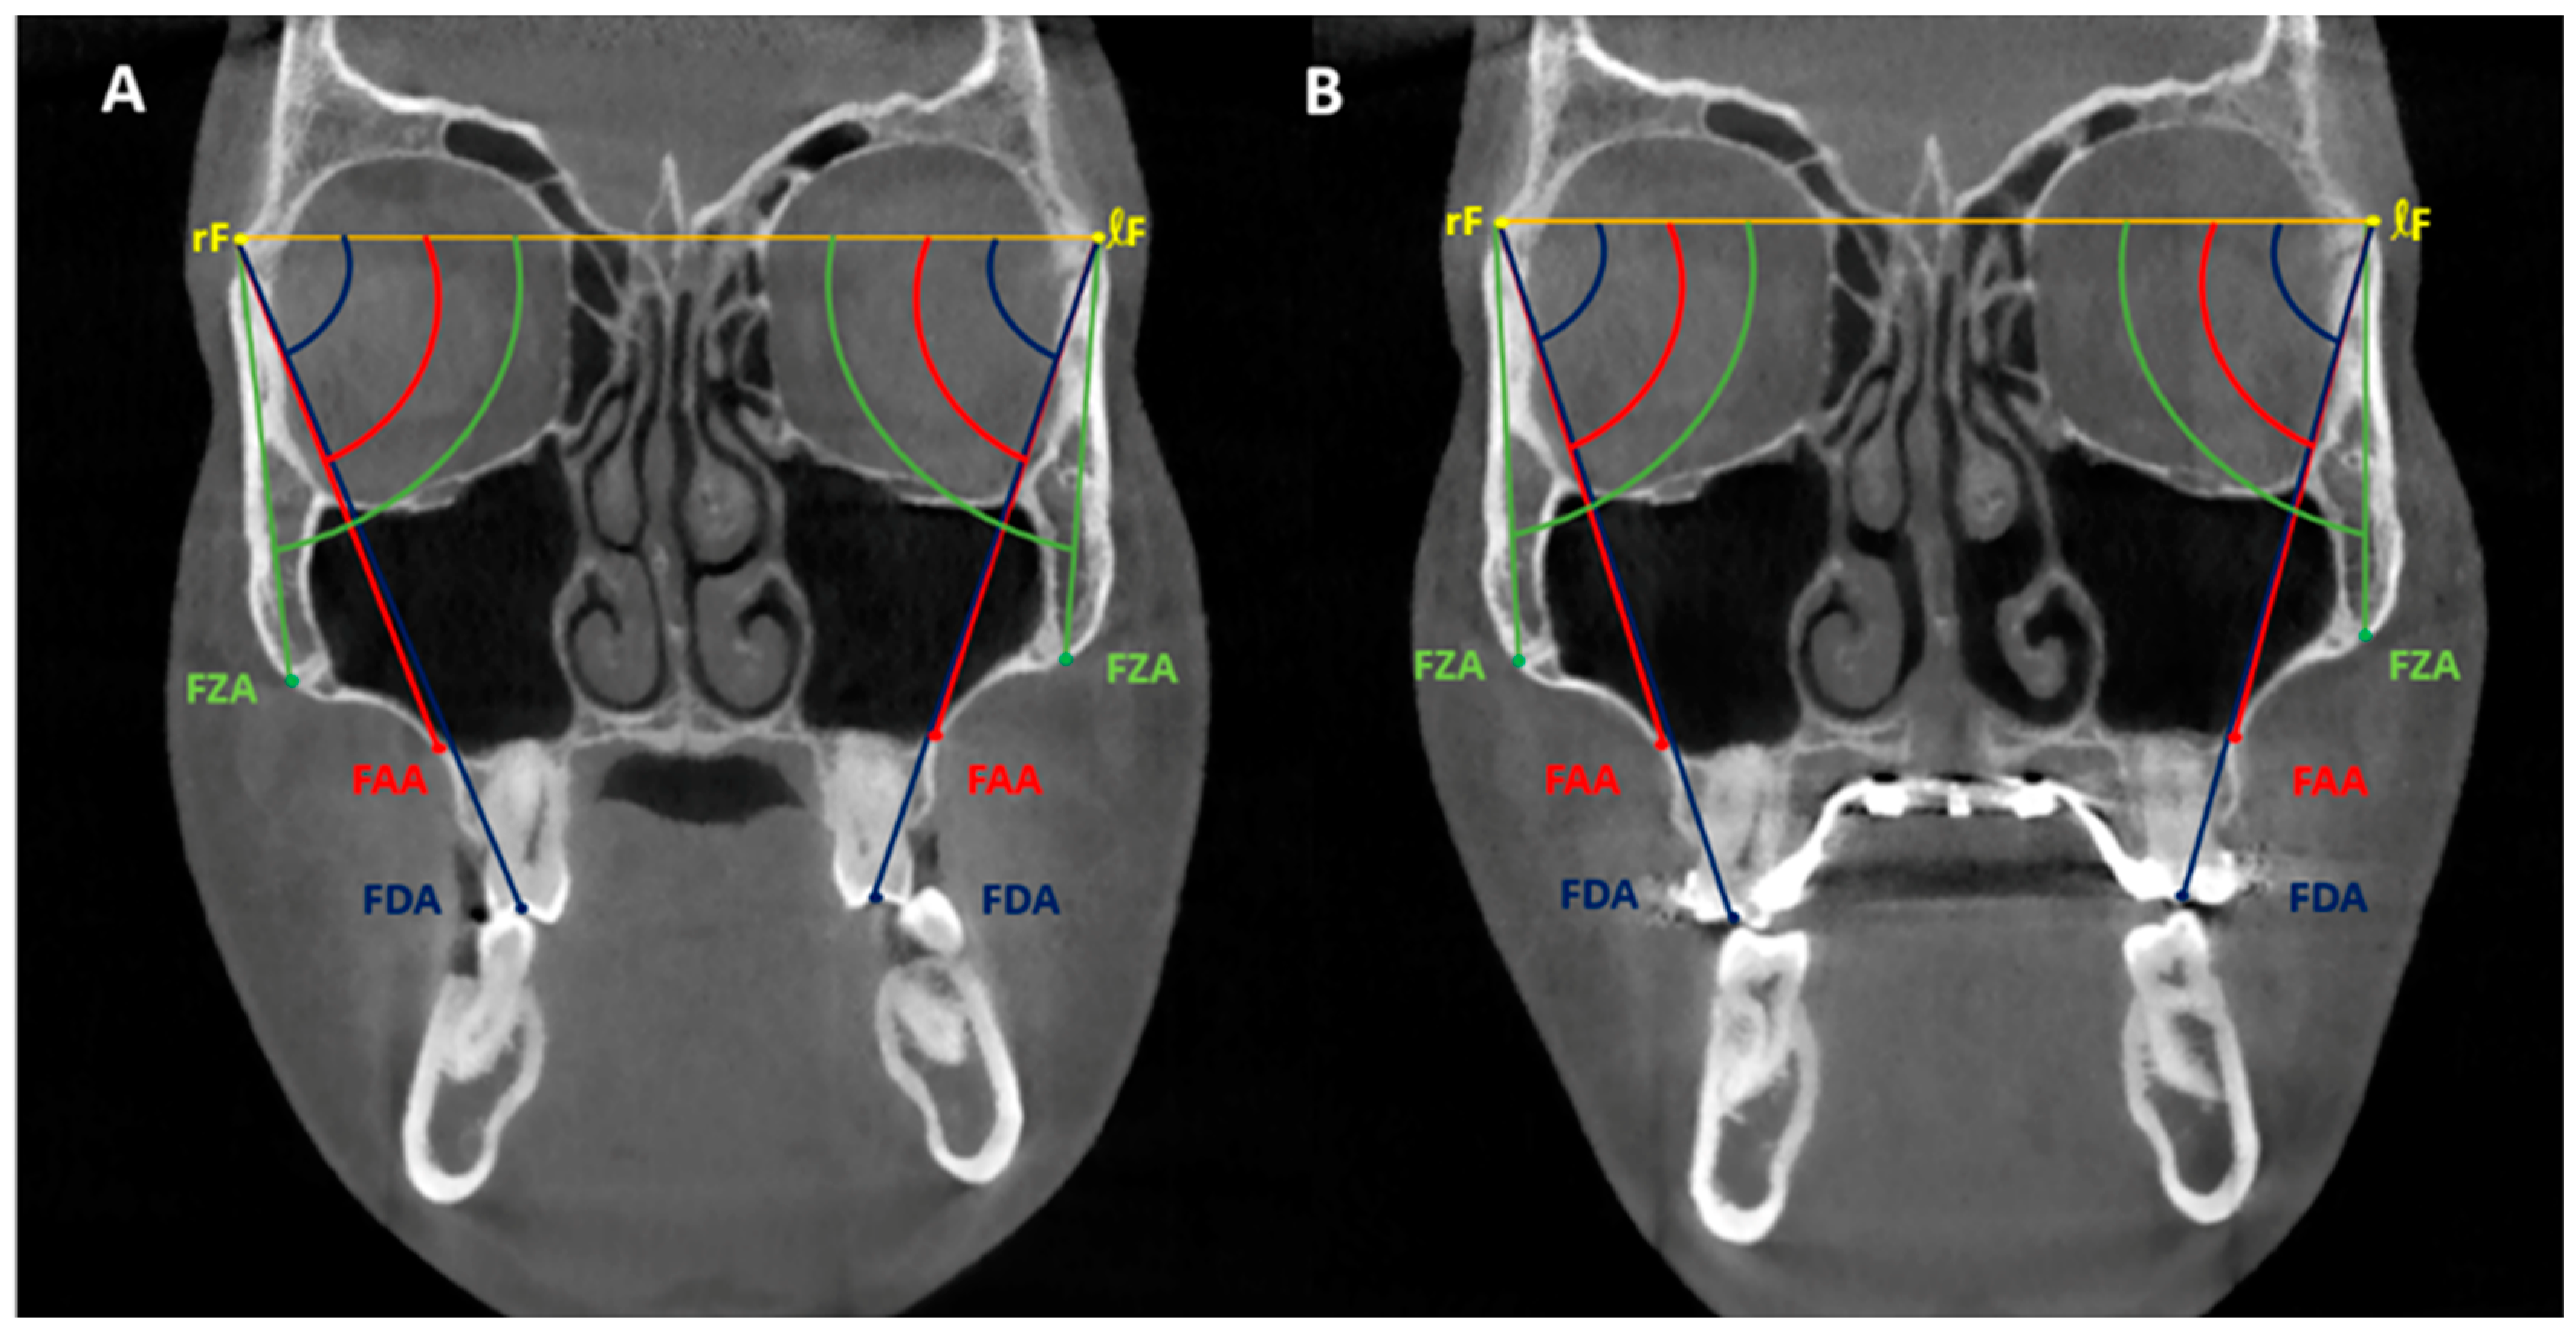

The true rotational fulcrum on the right and left sides (rF and lF) was found using a method previously described, and the interfrontal line was established by connecting rF and lF [32,33]. Then, the following angular measurements were performed to assess skeletal, alveolar, and dental components of expansion: (1) the frontozygomatic angle (FZA) between the interfrontal line and the line extending from fulcrum to the most external point of the zygomaticomaxillary suture, (2) the frontoalveolar angle (FAA) between the interfrontal line and the line extending from fulcrum to the alveolar bone surface at the level of distobuccal root tip of the upper first molars, and (3) the frontodental angle (FDA) between the interfrontal line and the line extending from fulcrum to the occlusal point located at the central groove of the upper first molar (Figure 3). These three angles were measured on right and left sides, and the pre-expansion value (T0) was subtracted from the post-expansion value (T1) in order to determine the treatment change for each section. The FZA changes correspond to zygomaticomaxillary expansion, a true skeletal expansion (FZA changes); the FAA changes correspond to the sum of skeletal expansion (FZA change) and alveolar bone bending (FAA changes–FZA changes); and the FDA changes correspond to the sum of skeletal expansion (FZA changes), alveolar bone bending (FAA changes–FZA changes), and dental tipping (FDA changes–FAA changes). In order to assess the long-term stability of MSE expansion, pre-expansion (T0) and post-treatment (T2) CBCTs were also superimposed using the method described, and all angular measurements described above were repeated to compare T0–T1 changes vs. T0–T2 changes.

Figure 3.

Angular measurement systems in the coronal zygomatic section: frontozygomatic angle (FZA); frontoalveolar angle (FAA); frontodental angle (FDA); rF, right fulcrum; ℓF, left fulcrum. Interfrontal line: yellow line connecting rF and ℓF. (A) Pre-expansion measurements. (B) Post-expansion measurements.